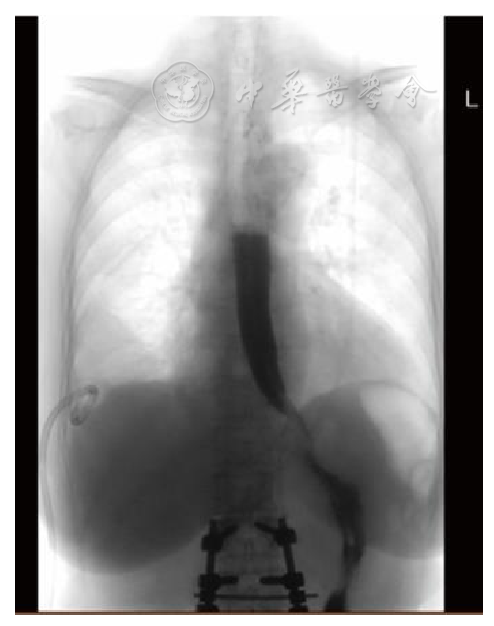

图3 术后复查CT 3A 腹腔镜食管裂孔疝术后第7天CT检查,见右侧胸腔积液较之前的影像明显增多,并伴有气体密度,同时可见相邻肺组织的明显压迫。膈肌区域出现气体和液体积聚,不能排除食管下段瘘的可能。3B 口服造影剂后CT检查(术后第8天)示食管下段存在瘘管,并且对比剂渗漏进入右侧胸腔